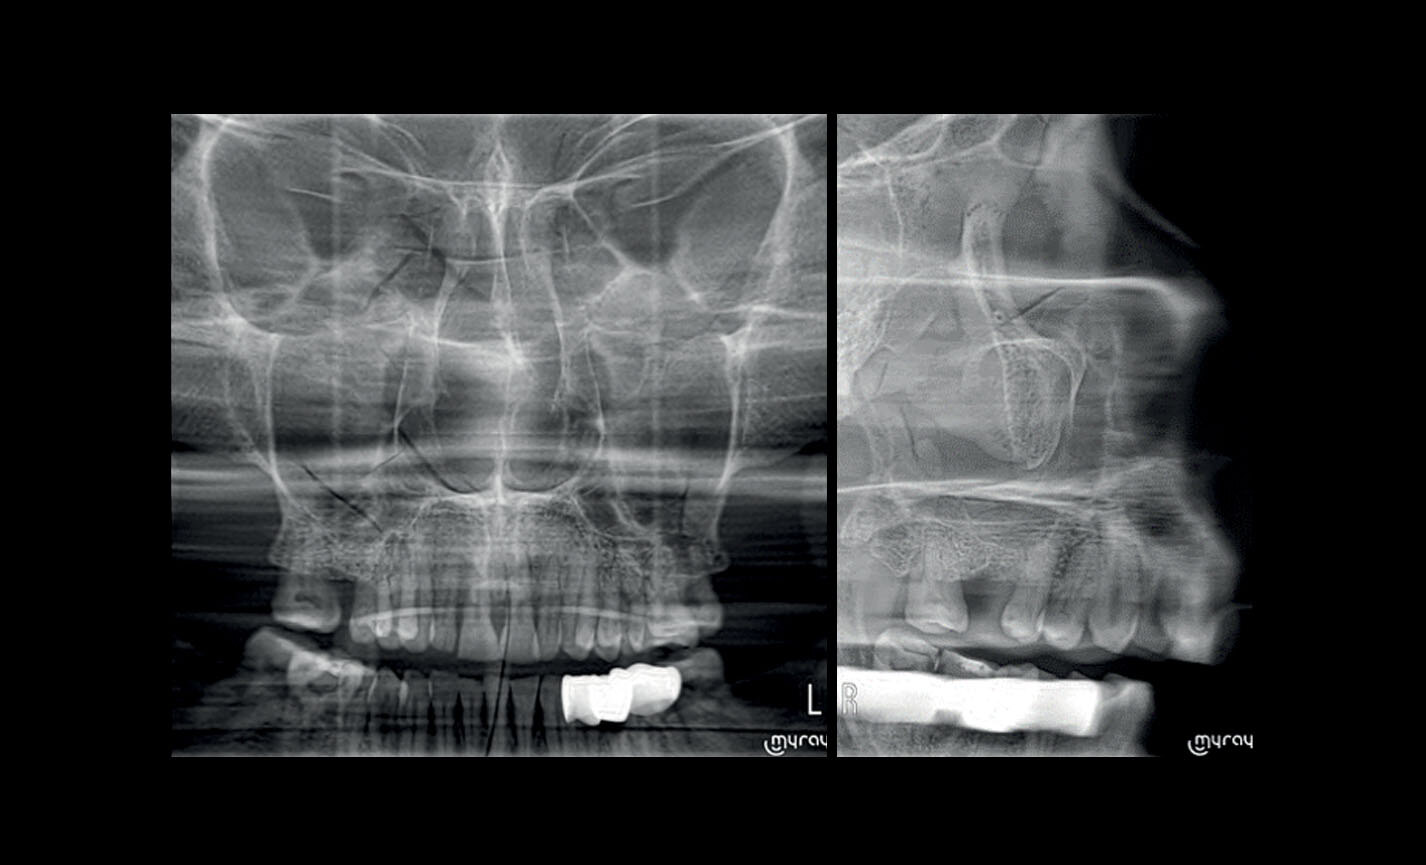

Téléradiographie

Latéro-latérale : avec détails des os et des tissus mous en évidence, fondamental pour les études céphalométriques.

Téléradiographie

Antéro-postérieure : pour investiguer les asymétries et les malocclusions en vue d’un traitement correct.

Applications orthodontiques

Des FOV de 10 cm de diamètre sont nécessaires pour l’étude des troisièmes molaires incluses car, chez un adulte de taille moyenne, la distance entre les troisièmes molaires de droite et de gauche, en incluant leurs racines respectives, le processus alvéolaire et l’os avoisinant, est d’au moins 9 cm. Les champs de vision réduits sont utiles en cas d’analyse de dents incluses ou surnuméraires, pour limiter la dose à la seule région d’intérêt. En effet, pour une planification correcte du traitement, il est fondamental de déterminer la position réelle (vestibulaire ou palatine), possible uniquement avec une analyse 3D, même à très faible dose avec un protocole QuickScan. Le champ de vision complet 13 x 16 cm permet une évaluation minutieuse des voies aériennes supérieures, souvent utile pour compléter une investigation en vue d’un traitement orthodontique qui tienne compte des problématiques oto-rhino-laryngologiques.